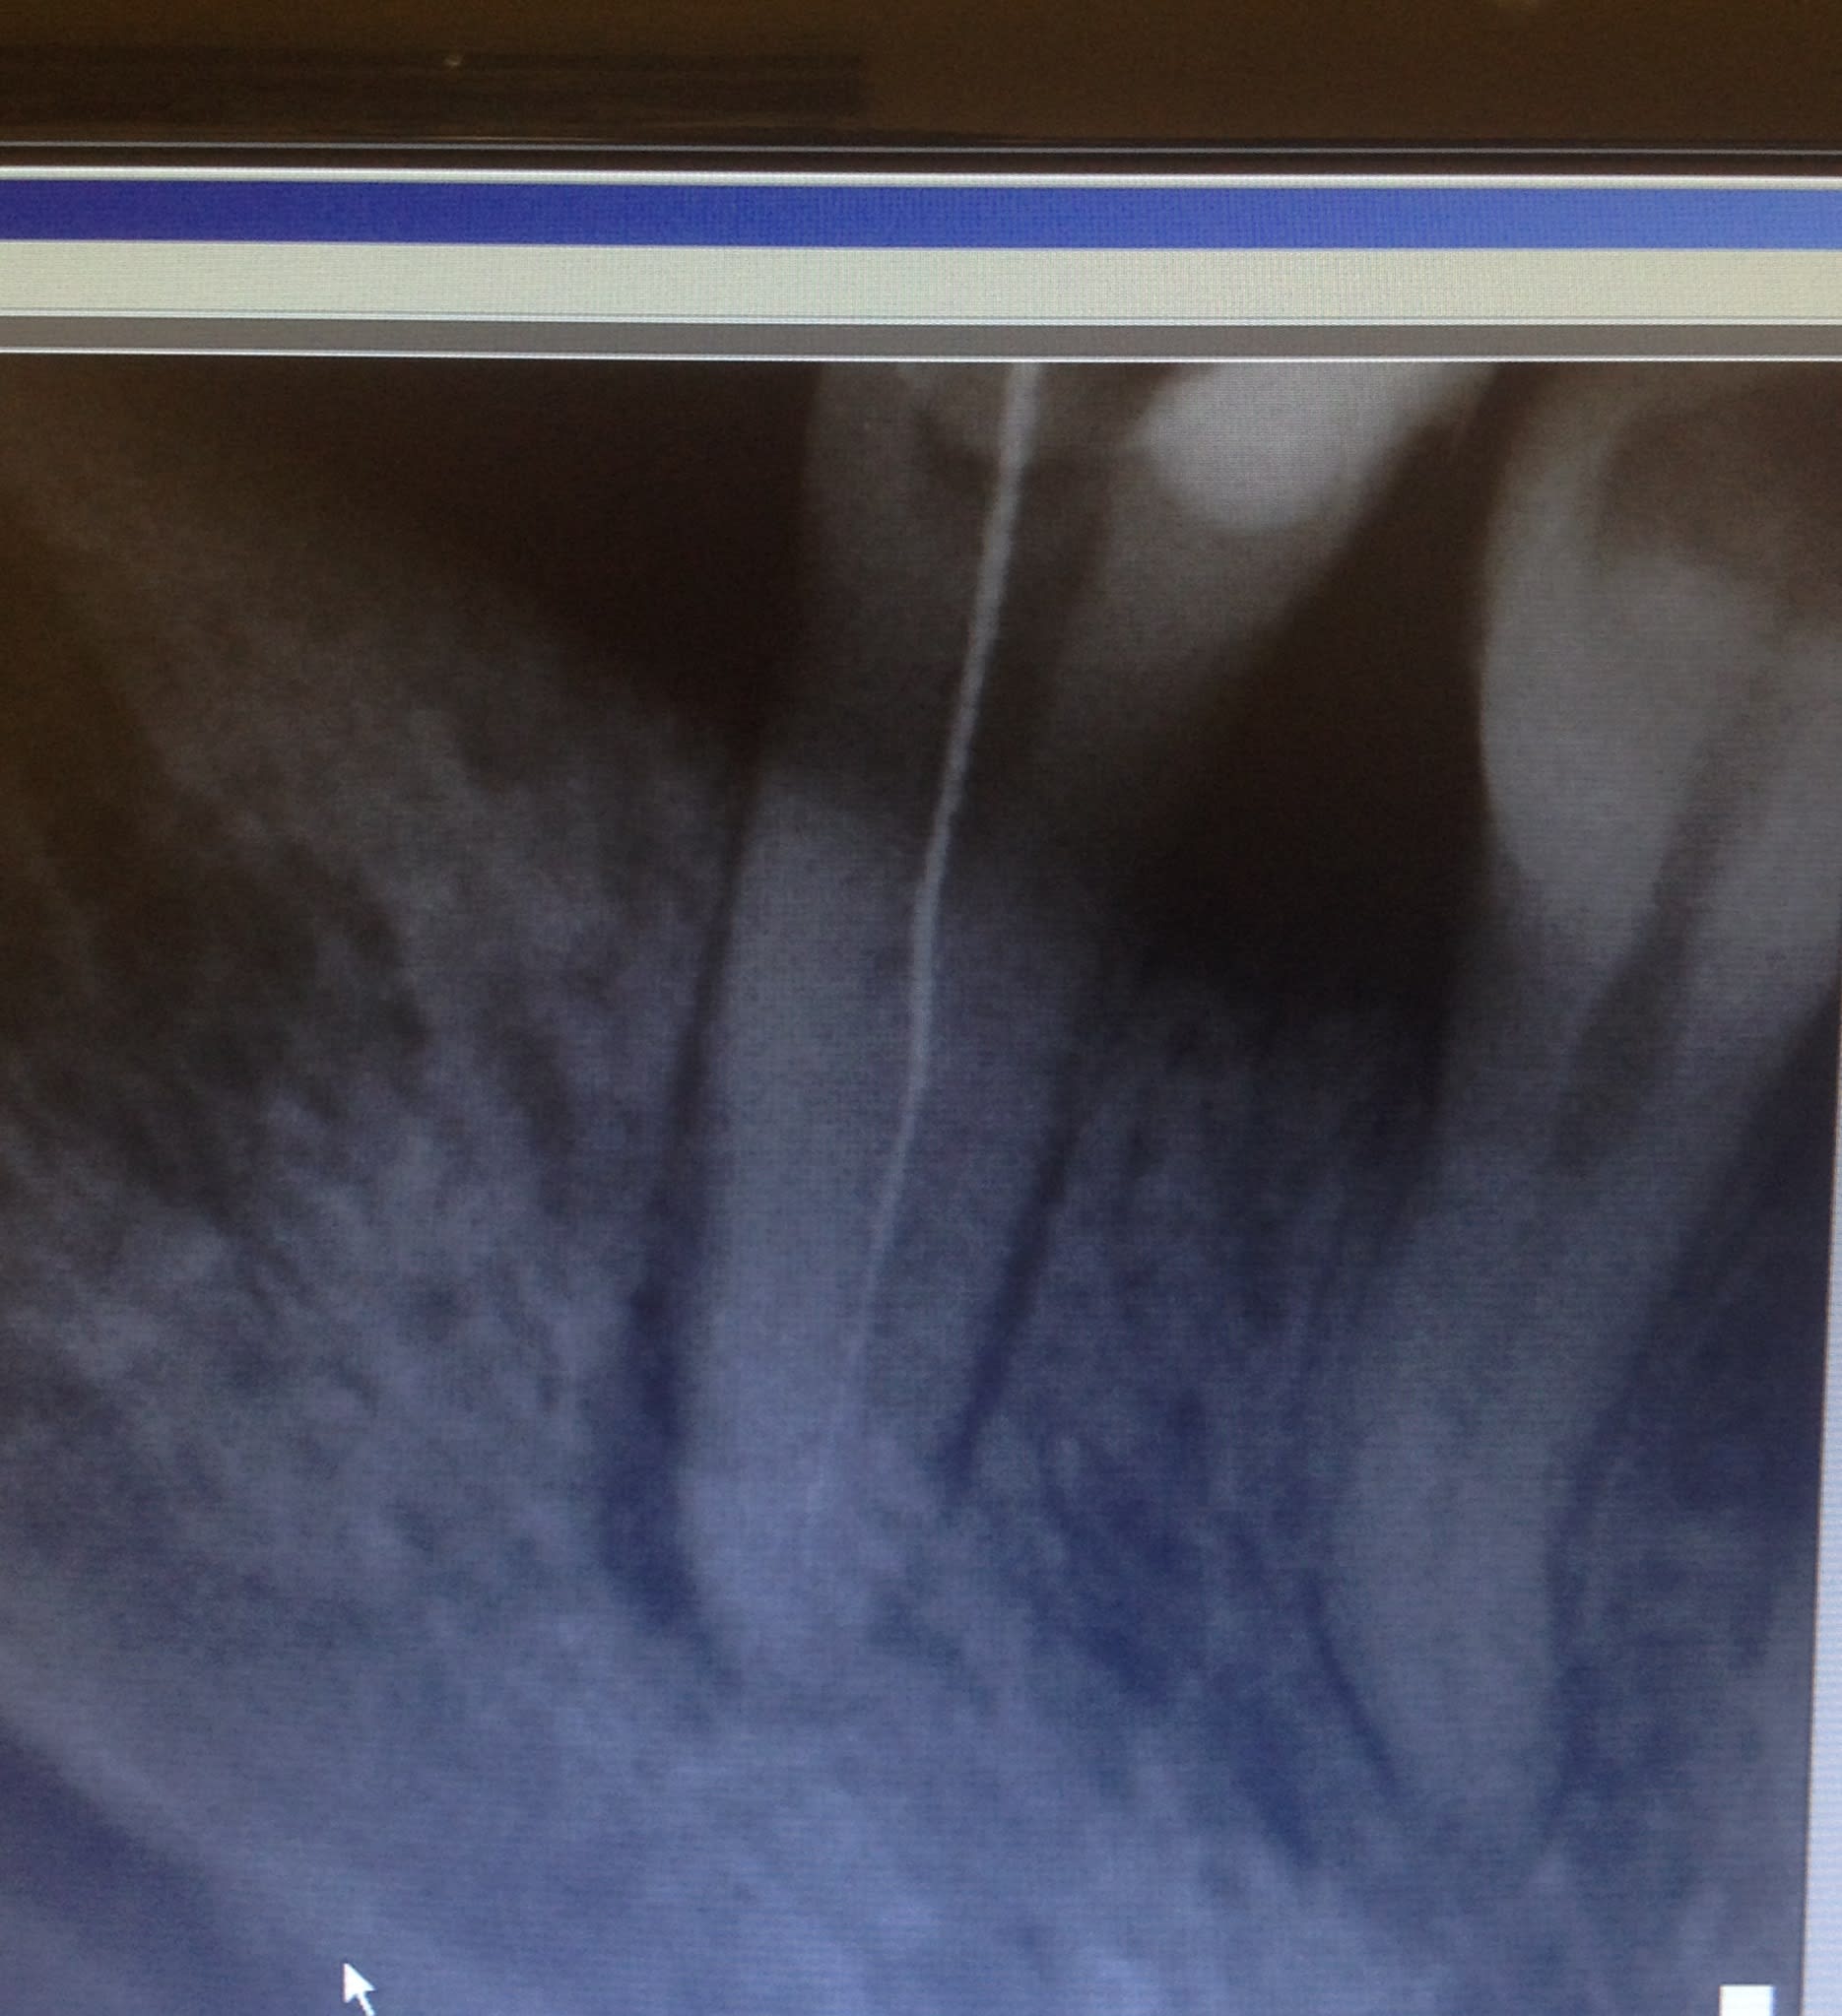

Sans micro, j'en ai un paquet des comme ça à mon actif... Elargissement du tiers coronaire à la congé fine, ultrasons, glyde, recherche de la bifurcation au Sx ou au S1, puis R25.

Sur une radio équivalente, j'ai déjà vu une 45 à 3 canaux, le plus dur c'est l'obturation pour pouvoir insérer simultanément les 3 cônes, je ne sais plus comment j'avais fait.

Sur ce cas, lime k 08 (06?) , k 10, k 15 puis s1, le sx est trop trapu des épaules à mon avis.

pas trop de glyde ou d'edta gel car ça favorise les fausses routes..

irrigation à fond et huile de coude. mais c est risqué quand même